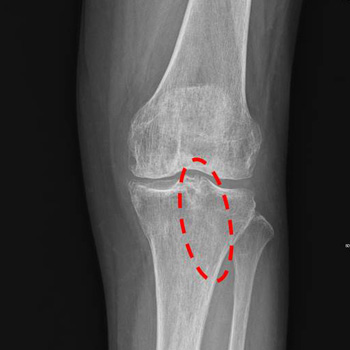

X-ray result

▲ After prayer: synostosis complete